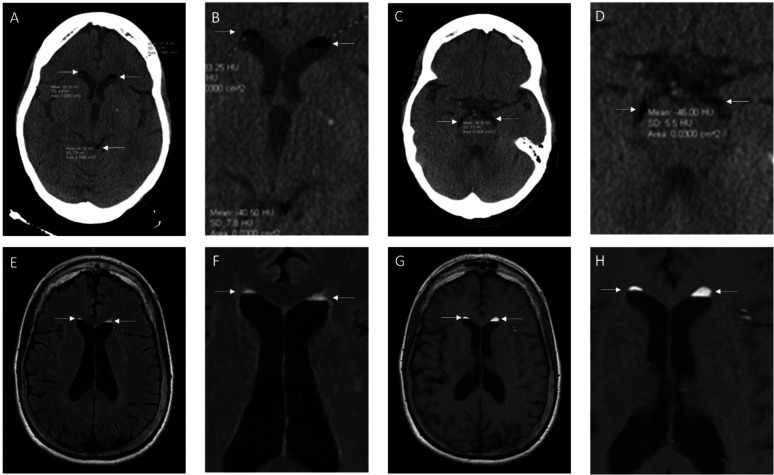

在大脑的脑脊液(CSF)空间中发现自由漂浮的脂肪滴是罕见的。当脂肪滴出现在脑脊液间隙时,最常见的原因是皮样囊肿破裂。皮样囊肿是先天性包涵性囊肿,在胚胎发生的第三至第五周神经管闭合期间形成。在这个病例报告中,我们描述了一个74岁的右撇子女性,她表现出急性视觉障碍和左手麻木。头部计算机断层扫描(CT)和磁共振成像(MRI)显示侧脑室和基底池低密度“病变”。CT Hounsfield单位在-41到-83 Hounsfield单位之间,与脂肪而不是空气兼容。T1加权和FLAIR MRI显示侧脑室脑脊液顶部“漂浮”的高强度病变,这是典型的脂肪滴,可能是由皮样囊肿破裂引起的。本病例强调了分析Hounsfield单位以区分病变密度的重要性,其中脂肪范围为-50至-150 Hounsfield单位,空气为-1000 Hounsfield单位。脑气是指硬膜外、硬膜下或蛛网膜下腔存在空气,可引起意识不清、恶心、癫痫发作和局灶性神经症状。仔细分析有或无MRI的CT神经影像学表现,对于正确诊断皮样囊肿破裂与脑积水是很重要的。

It is rare to find free floating fat droplets in the cerebral spinal fluid (CSF) spaces of the brain. When fat droplets are seen in the CSF spaces, the most common cause is the rupture of a dermoid cyst. Dermoid cysts are congenital inclusion cysts that form during the neural tube closure between the third and fifth weeks of embryogenesis. In this case report, we describe a case of a 74-year-old, right-handed female who presented with an acute onset of visual disturbances and left-hand numbness. Computed tomography (CT) and magnetic resonance imaging (MRI) of the head revealed hypodense "lesions" in the lateral ventricles and basal cisterns. The CT Hounsfield unit was between -41 to -83 Hounsfield Units, which is compatible with fat rather than air. The T1 weighted and FLAIR MRI showed hyperintense lesions "floating" on top of the CSF in the lateral ventricles, which is typical for fat droplets, presumably caused by a ruptured dermoid cyst. This case emphasizes the importance of analyzing Hounsfield Units to distinguish lesions by density, where fat ranges from -50 to -150 Hounsfield Units and air is -1000 Hounsfield Units. Pneumocephalus is the presence of air in the epidural, subdural, or subarachnoid space and can cause confusion, nausea, seizures and focal neurological symptoms. A careful analysis of the neuroimaging findings in the CT with or without MRI is important in making a correct diagnosis of a ruptured dermoid cyst versus pneumocephalus.